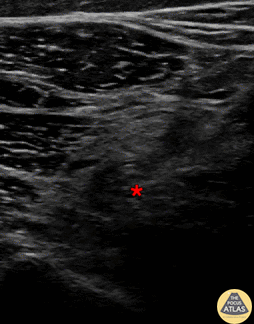

In-plane common peroneal nerve block at the level of the proximal fibula. The needle is seen first contacting the common peroneal nerve (*), then injecting anesthetic within the nerve perineurium. Denver Health Ultrasound Fellowship Archive